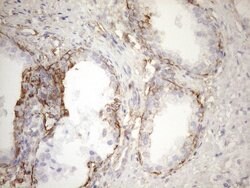

KRT16 Monoclonal Antibody (OTI1G1), TrueMAB™, OriGene

KRT16 is a member of the keratin gene family. The keratins are intermediate filament proteins responsible for the structural integrity of epithelial cells and are subdivided into cytokeratins and hair keratins. Most of the type I cytokeratins consist of acidic proteins which are arranged in pairs of heterotypic keratin chains and are clustered in a region of chromosome 17q12-q21. This keratin has been coexpressed with keratin 14 in a number of epithelial tissues, including esophagus, tongue, and hair follicles. Mutations in this gene are associated with type 1 pachyonychia congenita, non-epidermolytic palmoplantar keratoderma and unilateral palmoplantar verrucous nevus.Specifications

| Immunohistochemistry (Paraffin), Western Blot | |